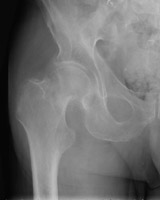

- Click on the image for a larger versionAAP radiograph of the left hip. This shows an incomplete fracture of the femoral head, Garden I in staging.